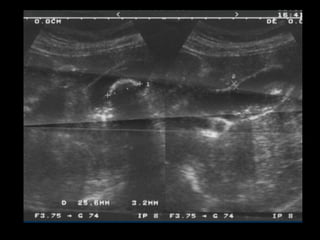

Colelitiasis

• Caracteristicas ecograficas

• Estructuras ecogénicas dentro de la luz

vesicular libre de ecos

• Sombra acustica con margenes “limpios”

• Dependencia gravitacional

• Son usualmente moviles